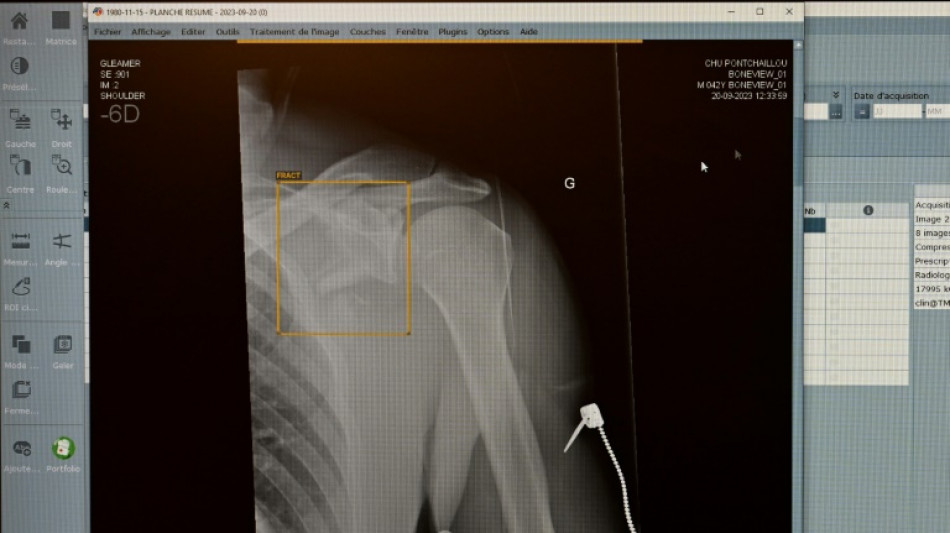

Jedes achte vom TÜV im vergangenen Jahr geprüfte medizinische Röntgengerät hat Mängel aufgewiesen. Die Gutachter stellten an 1893 der insgesamt rund 15.600 untersuchten Röntgengeräte Mängel wie etwa unzureichend gekennzeichnete Kontrollbereiche fest, wie der TÜV-Verband am Mittwoch in Berlin mitteilte. Die höchste Mängelquote wiesen Röntgengeräte in Zahnarztpraxen auf.

Insgesamt sank der Anteil der festgestellten Mängel im Vergleich zum Vorjahr aber von 16 Prozent auf zwölf Prozent. Dennoch fanden die TÜV-Gutachter 2849 einzelne Mängel. "Röntgenstrahlung ist niemals harmlos", erklärte Alexander Schröer, Strahlenschutzexperte des TÜV-Verbands. Geräte müssten daher nicht nur technisch einwandfrei funktionieren, sondern auch korrekt betrieben werden, "um die Strahlenbelastung für Patienten und medizinisches Personal zu minimieren".

Als "besorgniserregend" bezeichnete es der Prüfverband, dass jeder fünfte Mangel (19 Prozent) in die Kategorie der schwerwiegenden Mängel falle. Solche Geräte dürfen erst nach der Beseitigung der Mängel und einer neuerlichen Prüfung wieder in Betrieb gehen.

Gut jedes zweite (54 Prozent) der 2024 geprüften Röntgengeräte entfällt demnach auf die Zahnmedizin. 15 Prozent davon wiesen mindestens einen Mangel auf. Am häufigsten fielen ein mangelhafter Patientenschutz und unzureichend gekennzeichnete Kontrollbereiche auf, die dem TÜV zufolge aber wichtig zur Vermeidung unbeabsichtigter Strahlenexposition sind.

Die Mängelquote von Röntgengeräten in der Humanmedizin lag bei 13 Prozent und betraf etwa Bildwiedergabesysteme. Fehlerhafte Bildwiedergabesysteme gefährdeten die Diagnosesicherheit und könnten zu Fehldiagnosen oder unnötiger Strahlenbelastung führen. Die Mängelquote in der Veterinärmedizin lag ebenfalls bei 13 Prozent.